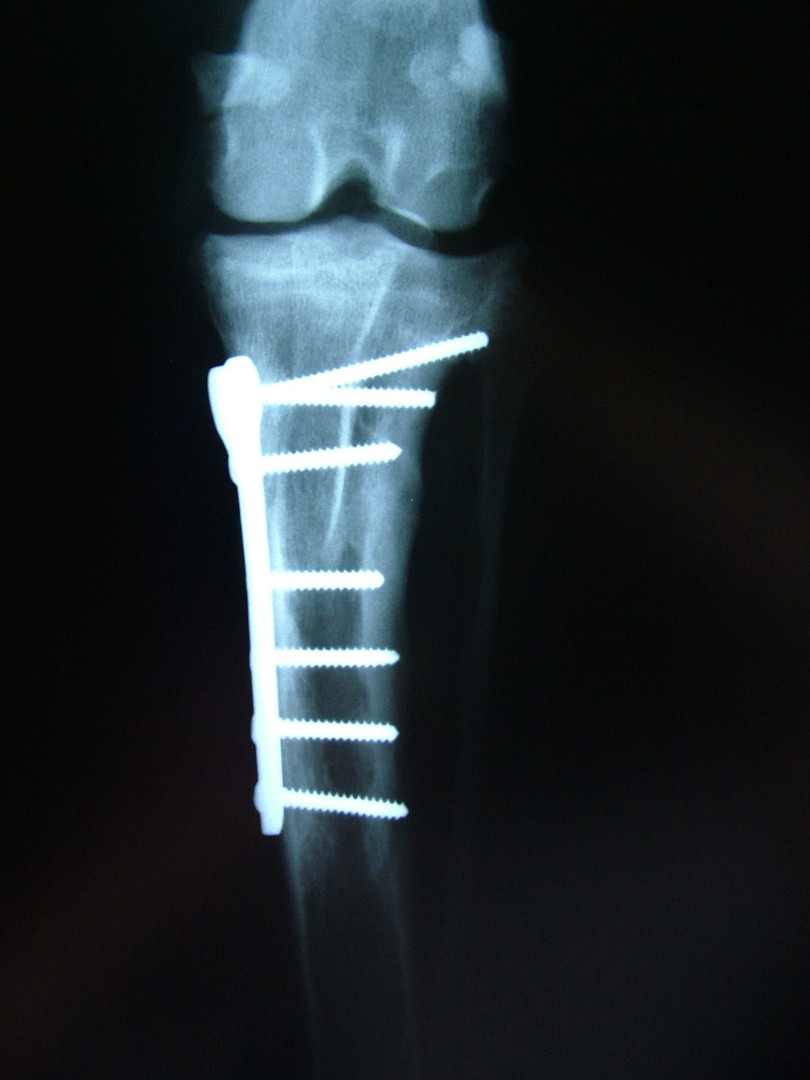

Az utóbbi 25 év egyik legnagyobb előrelépését jelentette a kereszteződőszalag szakadás műtéti megoldásában az amerikai származású Barclay Slocum által kifejlesztett műtéttechnika, mely alapja a szakadásra hajlamosító tényezők és a szalagra ható fizikai erők vizsgálata. Barclay Slocum olyan műtéti technikát dolgozott ki, mellyel a térdízületet az elülső kereszteződőszalagra ható erőkhöz igazítja. Vizsgálatai alapján a sípcsont ízületi felszínének meredeksége (tibia plató szög, tibial plateau angle, TPA) és az elülső kersztezőszalag szakadása között egyértelmű összefüggés mutatható ki. A műtét alapja, hogy a sípcsont ízületi felszínét a sípcsontból kivágott ék, majd azt követő lemezes osteosynthesis segítségével a sípcsont hossztengelyére megközelítőleg merőlegesre állítja be, csökkentve ezáltal a szalagra ható erőket (cranial wedge tibial osteotomy, CWTO).Ezt a technikát továbbfejlesztette: a sípcsonti ízületi felszín szögellésének korrekcióját egy speciális félkör alakú fűrész segítségével, az ízületi felszínt is magába foglaló sípcsonti részlet kivágásával, elforgatásával és rögzítésével oldatta meg (tibial plateau leveling osteotomy, TPLO).

Az utóbbi évek újítása a Slobodan Tepic által kidolgozott technika, mely a térdízületet alkotó szalagrendszert úgy alakítja át, hogy a térdízületre ható erők változnak meg és alakulnak a térdízülethez (Tibial Tuberosity Advancement, TTA).Mivel az eljárás még egészen új hosszú távú eredményessége még nem teljes körűen ismert.